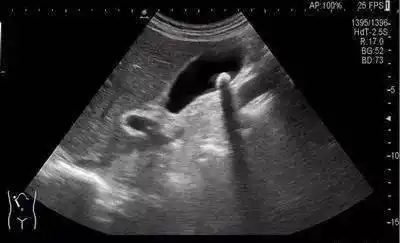

诊断 坏疽性胆囊炎伴穿孔 病例要点 超声上,复杂性或坏疽性胆囊炎可能